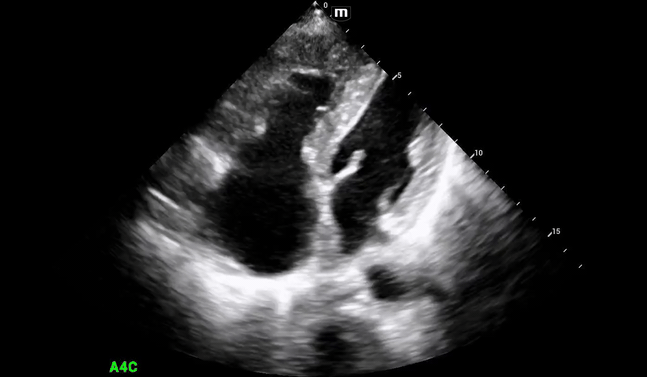

Additional views were obtained showing RV strain (likely chronic) in the PSS (below) as well as significantly enlarged RA and RV chambers, as noted in the A4C view (below).